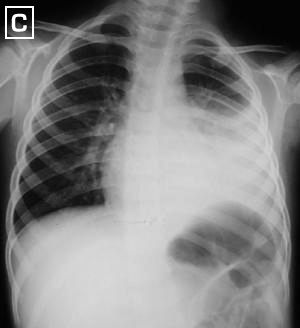

Rx. Tórax PA.(C). Aumento compensatorio del volumen pulmonar derecho, mayor aclaramiento del vértice y disminución de espacios intercostales del hemitórax izquierdo. retracción del diafragma izquierdo, escoliosis marcada por fibrotorax severo.